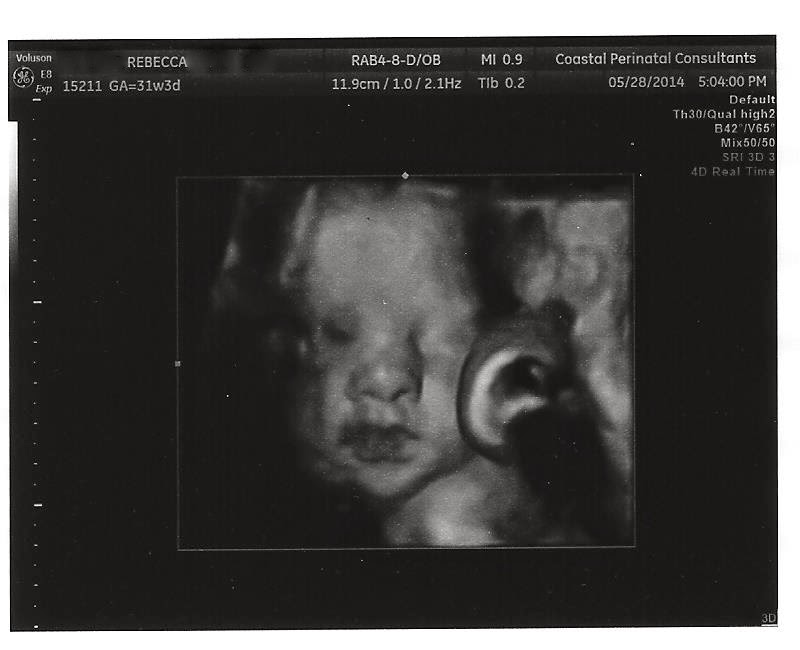

I normally don't like the 3D and 4D photos that are done of the babies as they really creep me out. Recently a friend posted one of her baby and it was terrible. I mean it looked like a puzzle badly put together. She had her's done at the same amount of weeks that I am now. Must be the machine that did the imagining was crappy. I was really surprised at how well the imaging came out yesterday. Still a bit creepy as Baby Hiccup decided to start opening up her eyes at the last frame.

I think she looks a lot like J when he was a baby. If I could fine a copy of the photo I know I put on this blasted computer to share with you of his baby photo I would but alas after 15 minutes of searching I can't find it. So annoying. At least I have two hard copies of his baby photo. Oh and she is smooshed up next to the placenta in the photos.